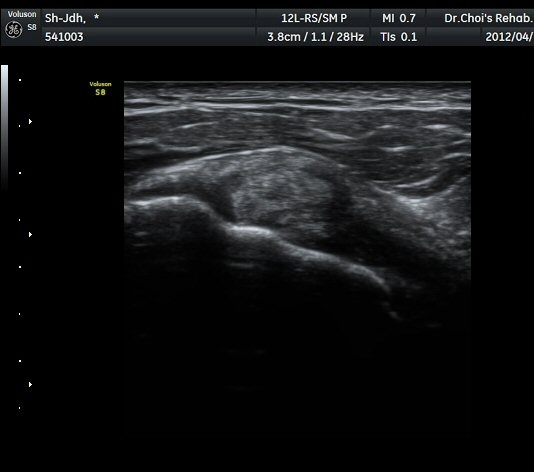

ŽÃËÀÚ¸¦ Á» ´õ µÚ·Î À̵¿ÇÏÀÚ °üÀý¼ø ³»Ãø °¡½Ã°üÀý¿À¸ñÆÐÀÓ(spinoglenoid notch)¿¡

¿øÇü¸ð¾çÀÇ Àú¿¡ÄÚ ³¶Á¾ÀÌ °üÂûµÊ(»çÁø 5, 6).